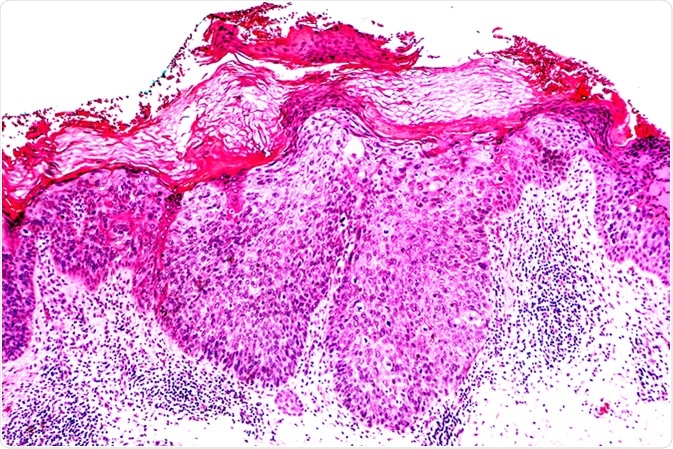

Cancer of Sun Damaged Skin: In squamous cell carcinoma in situ ("Bowen's disease"), malignant cells are confined to the epidermis, without invasion. Image Credit: David Litman / Shutterstock

- Biopsy of skin lesions is generally examined under microscope. This biopsy sample can distinguish Bowen's disease from other types of skin disorders. The sample should be taken correctly to eliminate squamous cell carcinoma, an invasive skin disorder to differentiate from Bowen's disease.